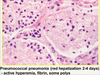

Candida bronchopneumonia

Lobar pneumonia on the left vs bronchopneumonia on right